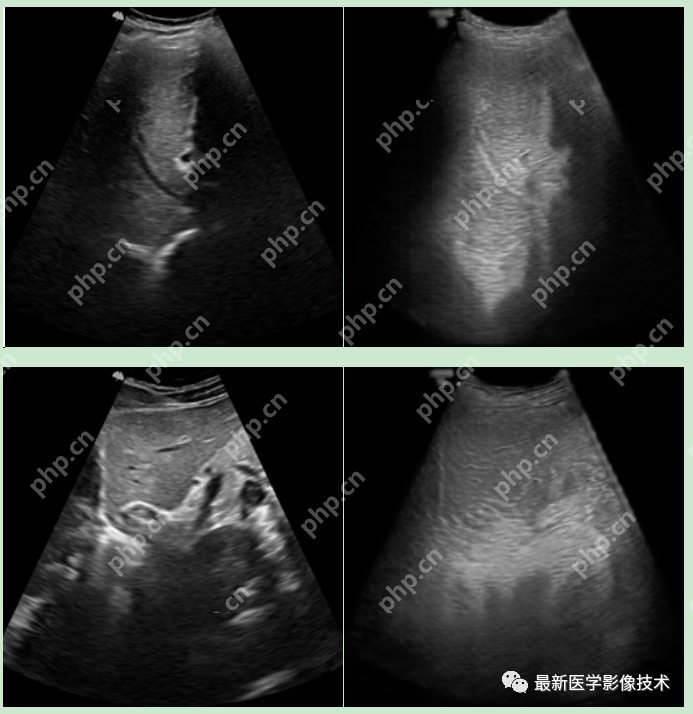

5、验证集部分生成结果

左图为低质量图像,中间为生成的高质量图像,右图为真实的高质量图像。